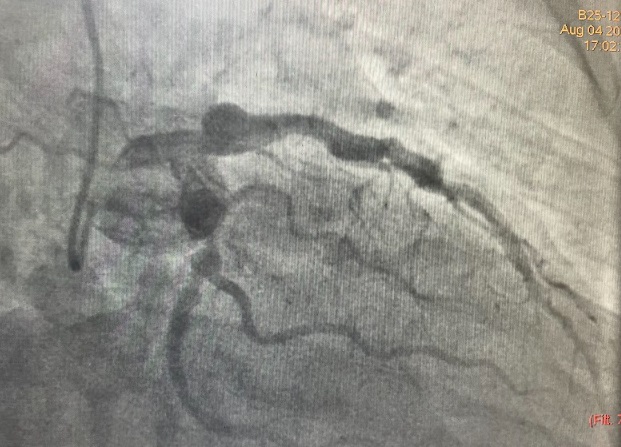

Coronary angiography showed a dominant RCA with a large proximal aneurysm measuring 4.5 ¡¿ 17 mm, with in-stent restenosis proximal to the aneurysm. Mid-to-distal RCA was ectatic. The LM, LAD, and LCx were also mildly ectatic but without significant stenoses. These findings were consistent with a giant RCA aneurysm, likely related to prior stent implantation.